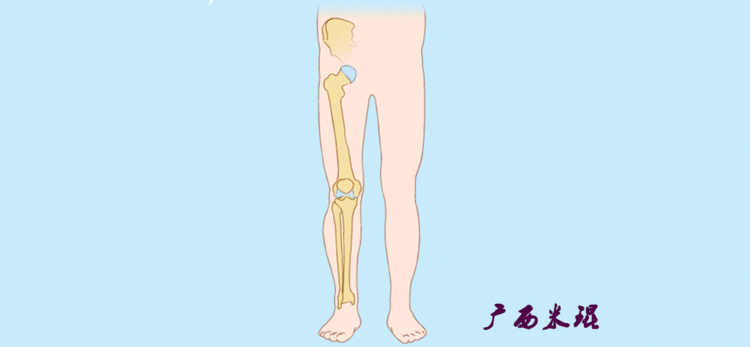

(2)机械轴机械轴是连接近端和远端关节中心点的直线。

机械轴要分前后位及侧位,站立前后位(也就是冠状面)股骨头中心与踝关节中心的连线通过膝关节中心,这是下肢的机械轴线,也就是下肢力线,常说Mikulicz线。冠状面的力线评估在临床工作中最常用、最基础、最重要。

站立侧位(矢状面)股骨头中心与踝关节中心的连线也通过膝关节中心,这也是下肢的机械轴线,这也是下肢力线。

矢状面的下肢力线常常被医生忽视,其实它的改变也是膝关节疼痛的常见原因。